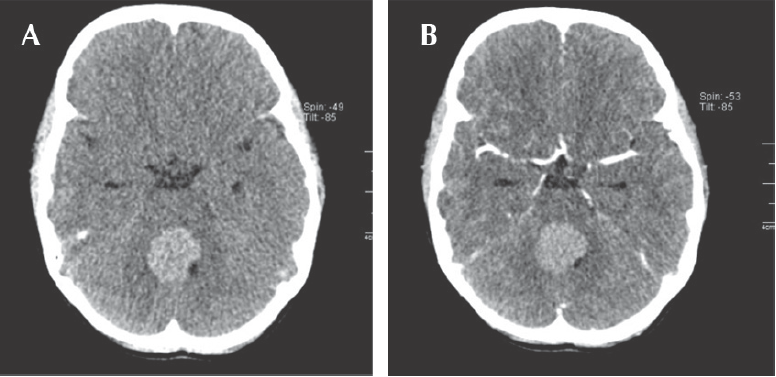

Niña de diez años, diez meses de edad, cuyo padecimiento tenía un mes de evolución e inició con vómito y ataque al estado general, se le trató como enfermedad acidopéptica sin mejoría. Tiempo después, la paciente presentó alteración de la marcha, por lo que se realizó tomografía axial computada de cráneo que mostró una zona hiperdensa en el cuarto ventrículo, que medía 2.5 x 3.5 cm y desplazaba rostralmente al tallo cerebral (Figura 1) La resonancia magnética mostró una lesión del cuarto ventrículo hipointensa homogénea, extraaxial, que reforzaba de forma difusa al contraste (gadolinio); sin infiltración aparente del cuarto ventrículo ni del pedúnculo cerebeloso por lo que se sospechó diagnóstico de meduloblastoma. (Figura 2) Lo anterior llevó a decidir una resección quirúrgica de la lesión en un 90% aproximadamente. Un informe transquirúrgico de patología informó de un tumor de células pequeñas, redondas y azules (Figura 3a). El informe histopatológico final fue de neoplasia maligna de estirpe linfoide con marcadores inmunohistoquímicos positivos para CD-45 (Figura 3b) y CD-20 (Figura 3c), base para el diagnóstico de linfoma difuso de células grandes B.

Figura 2 Resonancia magnética. A) Estudio simple en fase T1, corte axial: lesión intraventricular isointensa que condiciona obliteración parcial de la luz del cuarto ventrículo, así como compresión de puente y bulbo raquídeo. B) Estudio simple en fase T2 FLAIR, corte axial. C) Estudio contrastado en fase T1, corte axial: realce de forma homogénea posterior a la administración del medio de contraste. D) Fase T1, corte sagital con medio de contraste.